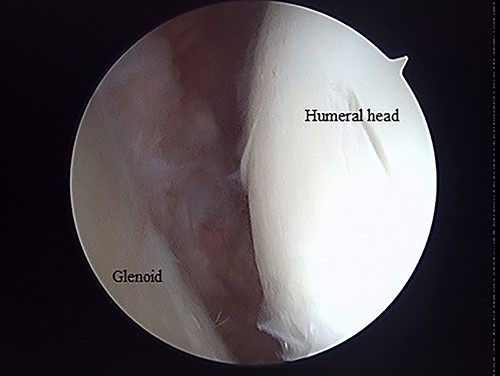

The operation was performed under general anesthesia with an ultrasound-guided brachial plexus block in the beach chair position. First, we performed intra-articular observation by arthroscopy with a 30° scope. Through a posterior portal, we confirmed incongruence of the articular surface of the humeral head, similar to the preoperative findings in 3D-CT (Fig. 4). On the other hand, the posterior joint labrum and glenoid rim were intact. After evaluating the intra-articular lesion, we performed arthroscopic reduction for the impression fracture at the humeral head via the arthroscopic method [5,6]. We split the deltoid muscle and exposed the lateral surface of the humerus. We inserted a Kirschner wire as a reduction guide 2 cm distal from the upper border of the greater tuberosity and 2 cm behind the bicipital groove (Fig. 5). Kirschner wire was inserted to exit the impression lesion while checking the articular surface with an arthroscope (Fig. 6). We created a cortical window (approximately 10 × 10 mm) using a cannulated drill with the Kirschner wire as a guide. To reduce the impression, we pushed the back of the impression using the flat side of the canulated cancellous screw (CCS) drill. After the reduction, artificial bone was inserted from the cortical window to the subchondral bone region to provide support for the depressed area. We then performed a procedure to insert a support screw into the articular surface. The deltopectoral approach was used. First, we dissected the subacromial bursa entirely while visualizing the conjoint tendon. Next, we detached the long head of the biceps at the bicipital groove and sutured it to the pectoralis major muscle. Two CCSs were inserted from the bicipital groove to under the repaired humeral head as support for the reduction site. Finally, after arthroscopic reduction, we performed ORIF for surgical neck fracture using a PHILOS Plate™ (DePuy Synthes).

Posterior arthroscopy of the right shoulder joint. The right is the humeral head side, and the left is the glenoid side. Impression of the humeral head was noted, but the posterior labrum was not damaged.